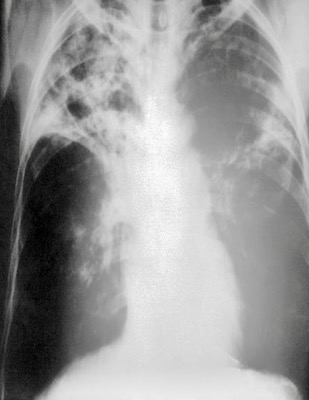

In France, Dr Jean-Antoine Villemin identified TB as a separate and communicable disease and presented his results at the 1867 Paris conference. Later, in Germany in 1882, Robert Koch identified Mycobacterium tuberculosis, which causes the disease, and in 1895, Wilhelm Rontgen discovered that X-Rays can be used to detect TB.